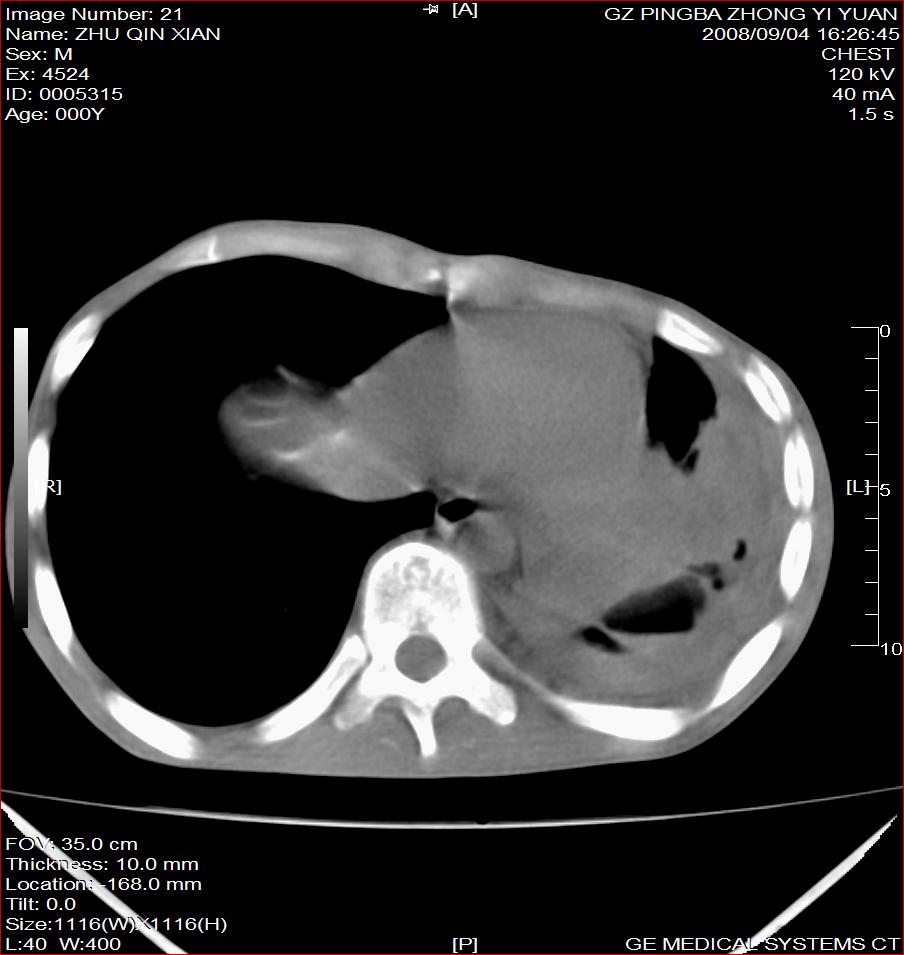

以下是引用随光逐影在2008-9-4 20:05:00的发言:[br]1)考虑两肺结核。2)左侧胸膜炎(胸膜肥厚、粘连,胸腔积液)。3)左侧局限性气胸。

以下是引用子十在2008-9-4 19:34:00的发言:[br]左上肺结核并空洞及双肺播散。节段性肺不张、胸腔积液、胸膜肥厚粘连。[br]